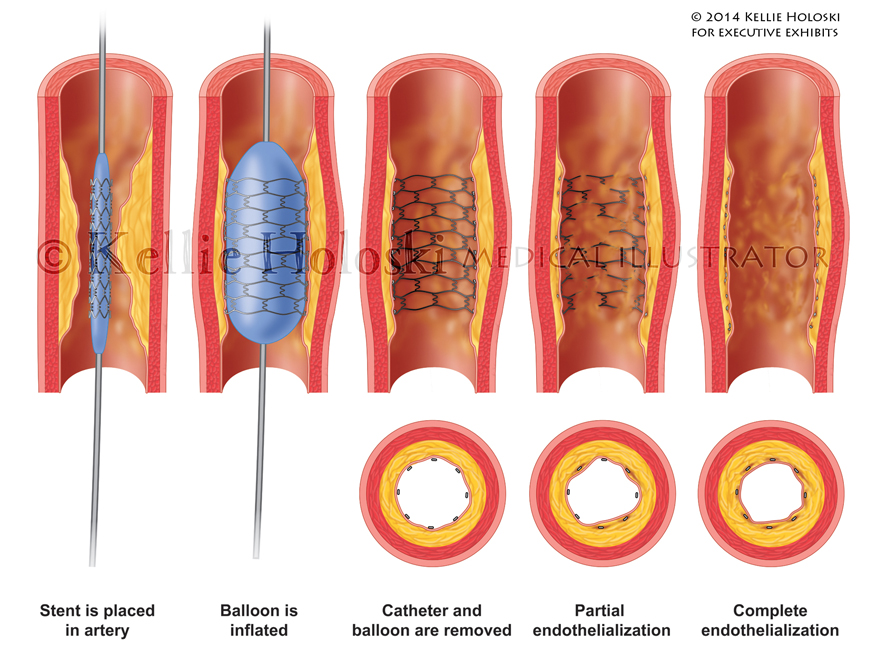

Endothelialization,

Adobe Photoshop

Courtroom exhibit for Executive Exhibits;

©Kellie Holoski -